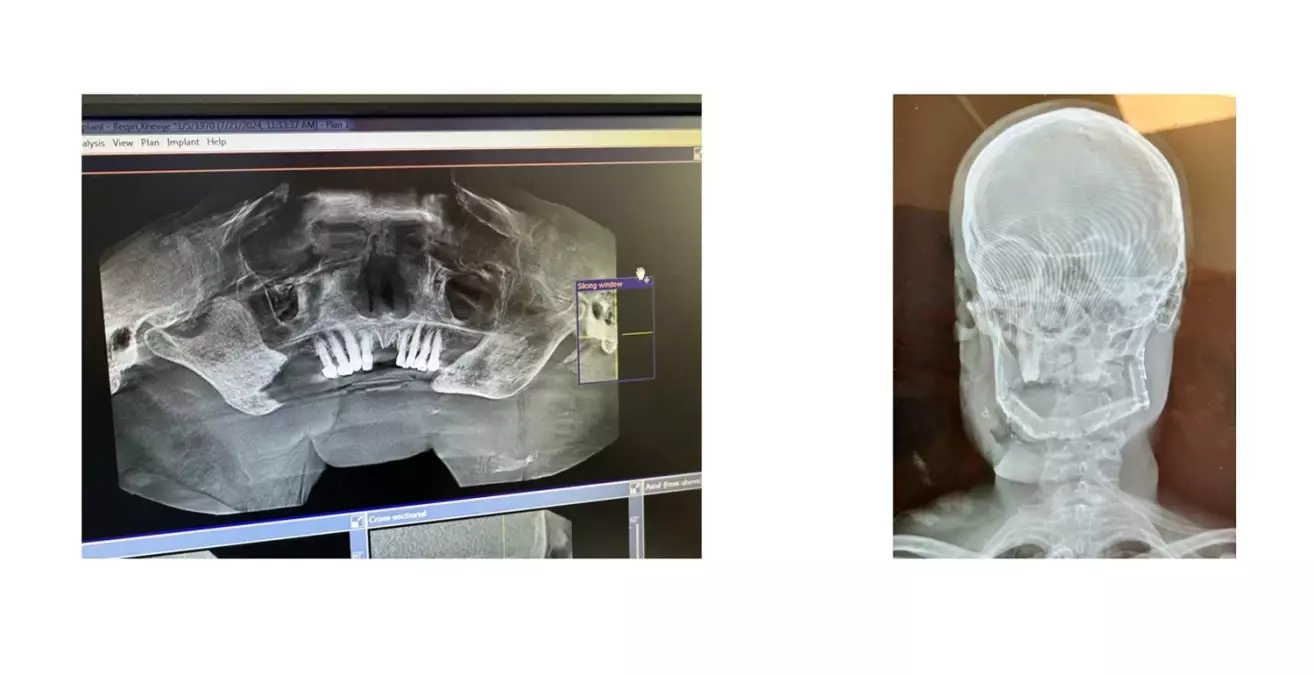

Plastik, Rekonstrüktif ve Estetik Cerrahi Uzmanı Prof. Dr. Osman Metin Yavuz, operasyonlar hakkında bilgi verdi. Yavuz, "Vakalar arasında, kanser olup yıllardır ameliyat edilemeyen, Kosova Cumhuriyeti Devleti tarafından bütçe ayrılarak, yurt dışında operasyon sırasını bekleyen hastalar da bulunuyordu. Çene kemiğini eriten büyüklükte ağız tabanı kanseri olan bir hasta, operasyon programına alındı. Tümör çıkarıldıktan sonra, bacaktan damarları ile hazırlanan, kemik ve deri dokusu, mikrocerrahi teknikle çene bölgesine taşındı ve damarlar mikroskop altında anastomoz edildi. Serbest flep cerrahisi olarak adlandırılan bu işlem, 15 saat sürdü. Ameliyata dahil olan Kosovalı cerrahlar, böyle bir ameliyatın bu coğrafyada ilk defa yapıldığını söylediler. Kosova'daki cerrahi ekip tarafından düzenli takipleri yapılan hastalarda herhangi bir sorun ve komplikasyon yaşanmadı. Gönüllü olarak katıldığımız bu aktivitede, Kosova'da başta çocuklar olmak üzere yıllardır hastalıkla mücadele eden kişileri eski sağlıklarına kavuşturduğumuz için hem mutlu hem de gururluyuz" dedi.